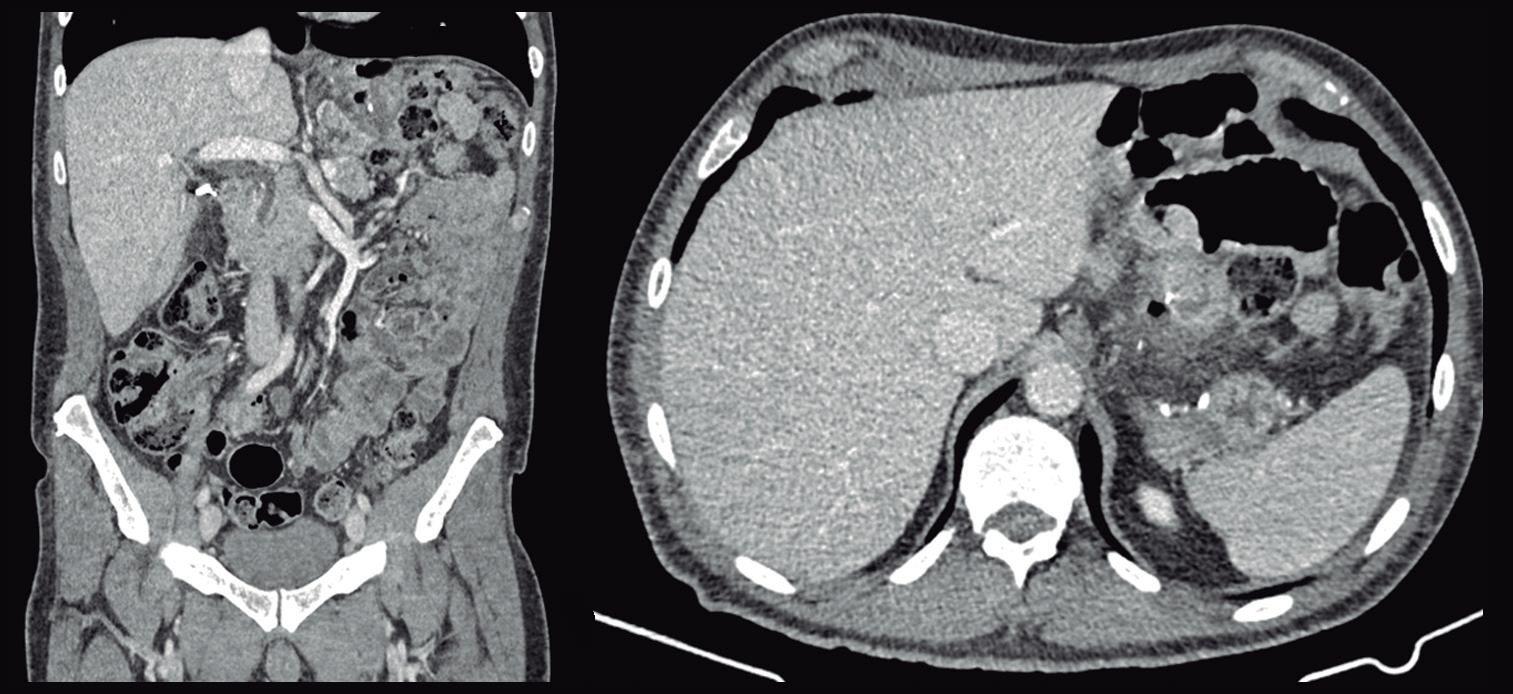

Masa oculta: reto diagnóstico en una adolescente con dolor abdominal agudo

Ivonne Loaiza Pacheco, Diana Marcela Rodríguez De la Hoz, Manuela Laguna Kirof, Nebil Larrañaga, Eugenia Orozco

Hidden Mass: Diagnostic Challenge in a Teenager with Acute Abdominal Pain